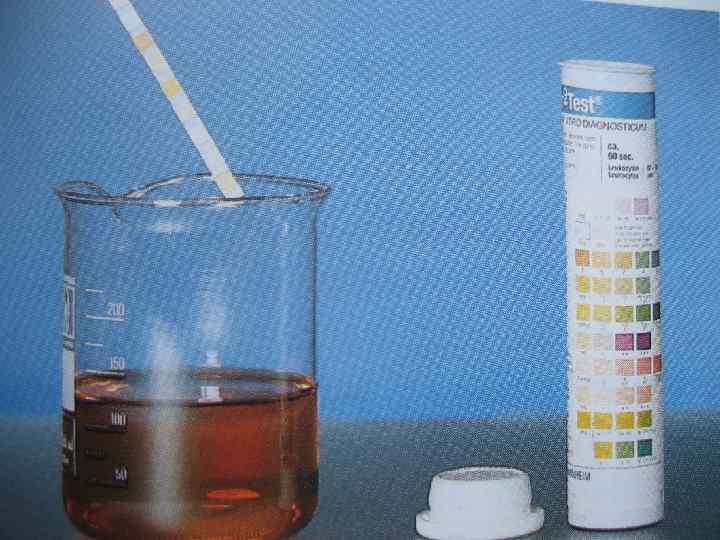

• • Опухоль м/п Диагностика Гематурия Учащенное мочеиспускание Осмотр пациента Дополнительные методы: ВВУ УЗИ СT Сканирование костей • Цитология мочи • Цистоскоция и ТУР 20